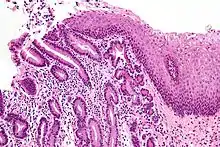

A micrograph of Barrett's esophagus.

Barrett's esophagus is an abnormal change in the cells of the lower esophagus, thought to be caused by damage from chronic stomach acid exposure.